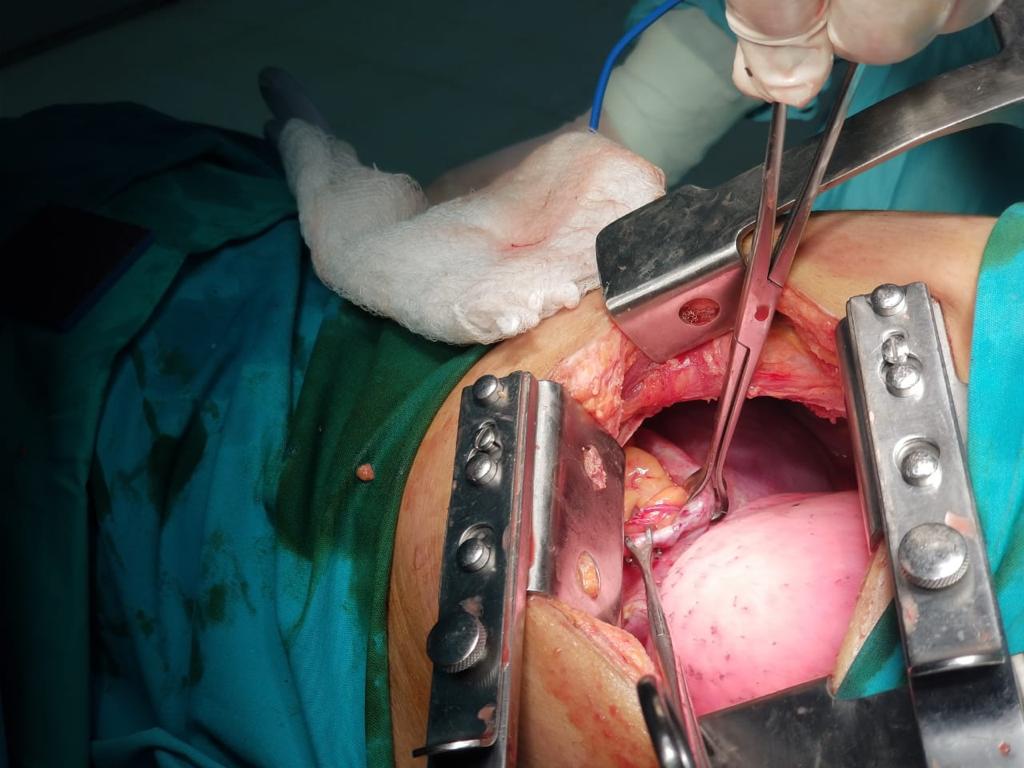

Figure 3. Surgeon's view through a left poetrolateral thoracotomy. Babcock grasping the stomach surrounded by omentum.

The patient was urgently taken to the operation theater and a left posterolateral thoracotomy incision was placed. After dividing the subcutaneous fat and muscle, the seventh intercostal space was entered. Contents of the hernia were visualized in the chest cavity and were manually reduced using digital compression. A loop-shape defect measuring approximately 15 cm in length was identified in the anterolateral part of the muscular portion of the diaphragm. The defect was repaired in three layers using a Prolene® 1 suture in a continuous fashion.